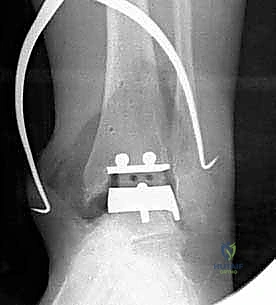

- المكون الظنبوبي (Tibial Component): صفيحة معدنية مسطحة من سبائك الكوبالت والكروم (Cobalt-Chromium)، تُثبت في أسفل عظمة الساق (الظنبوب) بواسطة أسطوانتين معدنيتين تدخلان في العظم لضمان الثبات المطلق.

- المكون الكاحلي (Talar Component): قطعة معدنية تغطي قبة عظم الكاحل، مصممة بشكل تشريحي منحني يحاكي تماماً شكل العظمة الأصلية، وتحتوي على أخدود طولي.

- الحشوة البلاستيكية المتحركة (Mobile Polyethylene Bearing): هذا هو سر نجاح غرسة STAR. هي قطعة من البلاستيك الطبي عالي الكثافة (UHMWPE) توضع بين القطعتين المعدنيتين. هذه القطعة ليست ثابتة، بل تنزلق بحرية للأمام والخلف، وتسمح بدرجة طفيفة من الدوران. هذا التصميم "المتحرك" يقلل بشكل هائل من إجهاد القص (Shear Stress) على واجهة العظم والمعدن، مما يقلل من احتمالية تخلخل الغرسة (Loosening) على المدى الطويل، ويمنح المريض نطاق حركة فسيولوجي مذهل.

تعتمد دقة الجراحة على المحاذاة الصحيحة. يتم استخدام أجهزة توجيه متطورة (Jigs) تثبت على عظمة الساق باستخدام دبابيس معدنية. يتم التحقق من صحة الزوايا والمحاور باستخدام جهاز الأشعة السينية المباشر داخل غرفة العمليات (C-arm Fluoroscopy). يضمن الدكتور هطيف أن يكون القطع موازياً للأرض تماماً عند وقوف المريض.